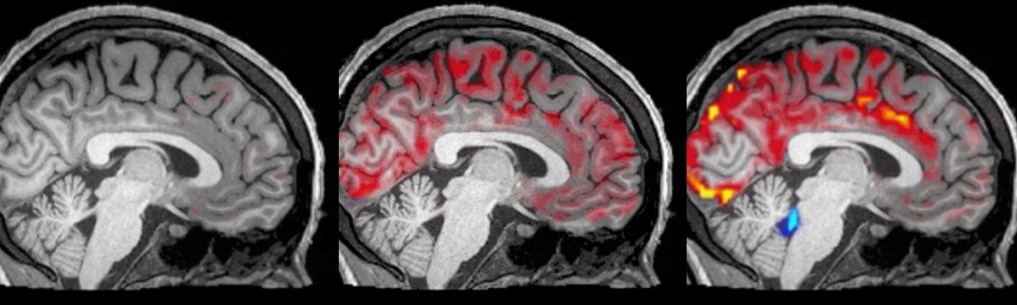

波士頓大學的科學家們史無前例地拍下了清洗過程:紅色是血液,藍色是腦脊液。厲害的是從前沒有發現過,血液會周期性地大量流出大腦。每當血液大量流出,腦脊液就趁機發動一波攻擊。腦脊液進人之後會清除毒素。

而這樣的清洗,只有在睡著後才能做到,讓人一覺醒來,擁有—個清爽的大腦;沒睡著的時候,腦脊液並沒有充分的機會趁虛而入去清除毒素。所以,多睡一點,不要熬夜了。

Source: Fultz et al 2019